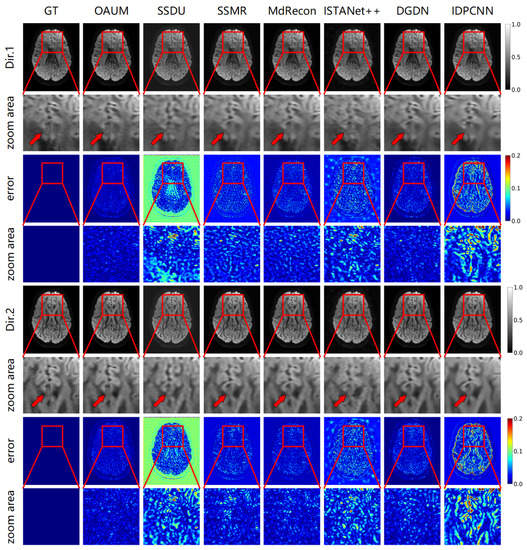

Figure 4 shows the DWIs reconstructed using the proposed model (OAUM) and various comparison models under 4-fold accelerated sampling, along with their respective ground truth (GT) images. For clarity, reconstruction results in two gradient directions are presented in Figure 4, and all results were normalized for consistency. Our method (OAUM) outperforms both self-supervised and supervised methods in terms of image quality improvement in both the gradient directions. Compared to the ground truth full-sampled data, OAUM has the smallest residual error when reconstructing DW images while exhibiting clearer details and textures that can be observed through red arrow areas. IDPCNN and ISTANet++ exhibit poor reconstruction performance at the brain structure edges, while SSDU performs poorly in background regions and skull edges. Although SSMR, MdRecon, and DGDN have acceptable residual ranges, their residual values are still larger than those of our proposed method when compared side-by-side.

Figure 4. The DWIs reconstructed from models with acceleration factor (AF) = 4 and two diffusion gradient directions.

Table 1 shows the quantitative evaluation results, which demonstrate that our proposed model achieved superior results. Specifically, it obtained the highest PSNR and SSIM values while also having the lowest RMSE value. Compared to DGDN, a suboptimal method, OAUM reduced the RMSE by 33% and increased the PSNR and SSIM by 8% and 25%, respectively. These findings suggest that DW images reconstructed using OAUM are more accurate representations of real images. In addition, we also show the minimum computational complexity of each model in Table 1. It can be seen that this model has a relatively high minimum computational complexity. It is worth noting that our proposed method reconstructs diffusion-weighted images with 64 gradient directions at the minimum computational complexity, while the compared method only reconstructs diffusion-weighted image with only 1 gradient direction.

Figure 5 demonstrates the reconstruction effect of our model at a higher sampling rate. The figure shows the reconstructed DWIs of each model and its residual images compared to the true fully sampled image at an 8-fold acceleration factor (sampling rate of 0.125). Our method outperformed all other methods in detail recovery, as shown by the red arrow in the DW image. Comparing the Dir.1 and Dir.2 directions, OAUM exhibited a worse performance in the Dir.2 gradient direction than the Dir.1 direction because Dir.2 DWIs were reconstructed from q-space undersampled data. However, compared to self-supervised method SSDU and supervised methods ISTANet++ and IDPCNN, OAUM still had significantly lower errors, demonstrating its superiority.

Figure 5. The DWI results reconstructed from models with acceleration factor (AF) = 8 and two diffusion gradient directions.

Table 2 gives the quantitative evaluation results for reconstructing DW images using various methods with an 8-fold acceleration factor. The results indicate that our method is superior, while the MdRecon method is inferior under this level of sampling. Our method outperforms the suboptimal approach by achieving an 18% improvement in RMSE and a 5% increase in PSNR.